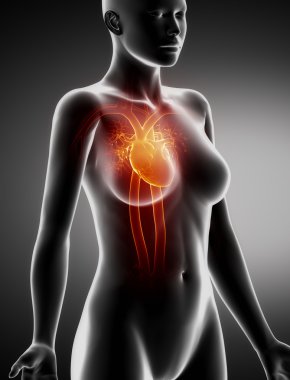

Kalbin anatomik incelemesi. Kalp sorunları, kalp krizi. Ameliyat mı? 3D görüntüleme. Siluet. Kalp, dolaşım sisteminin kan damarlarına kan pompalayan kaslı bir organdır.

Kırmızıİzole edilmişİnsanSağlıkBaşıİlaçSağlık hizmetlerierkekTıbbidikkatAdamsiyahYapıKardiyolojikalpHastagövdeKarnıEğitimİçeridebiyolojiBilimSistemGöğüsSaldırın!AcıorgvenKasÇizelgeİskeletanatomiKas gücübeyindiyagramBilim kurgux ışınısindirimAğrıKardiyakiskeletanatomikkoronerkalp krizi3d oluşturmakaslı organBenzer İçerikler